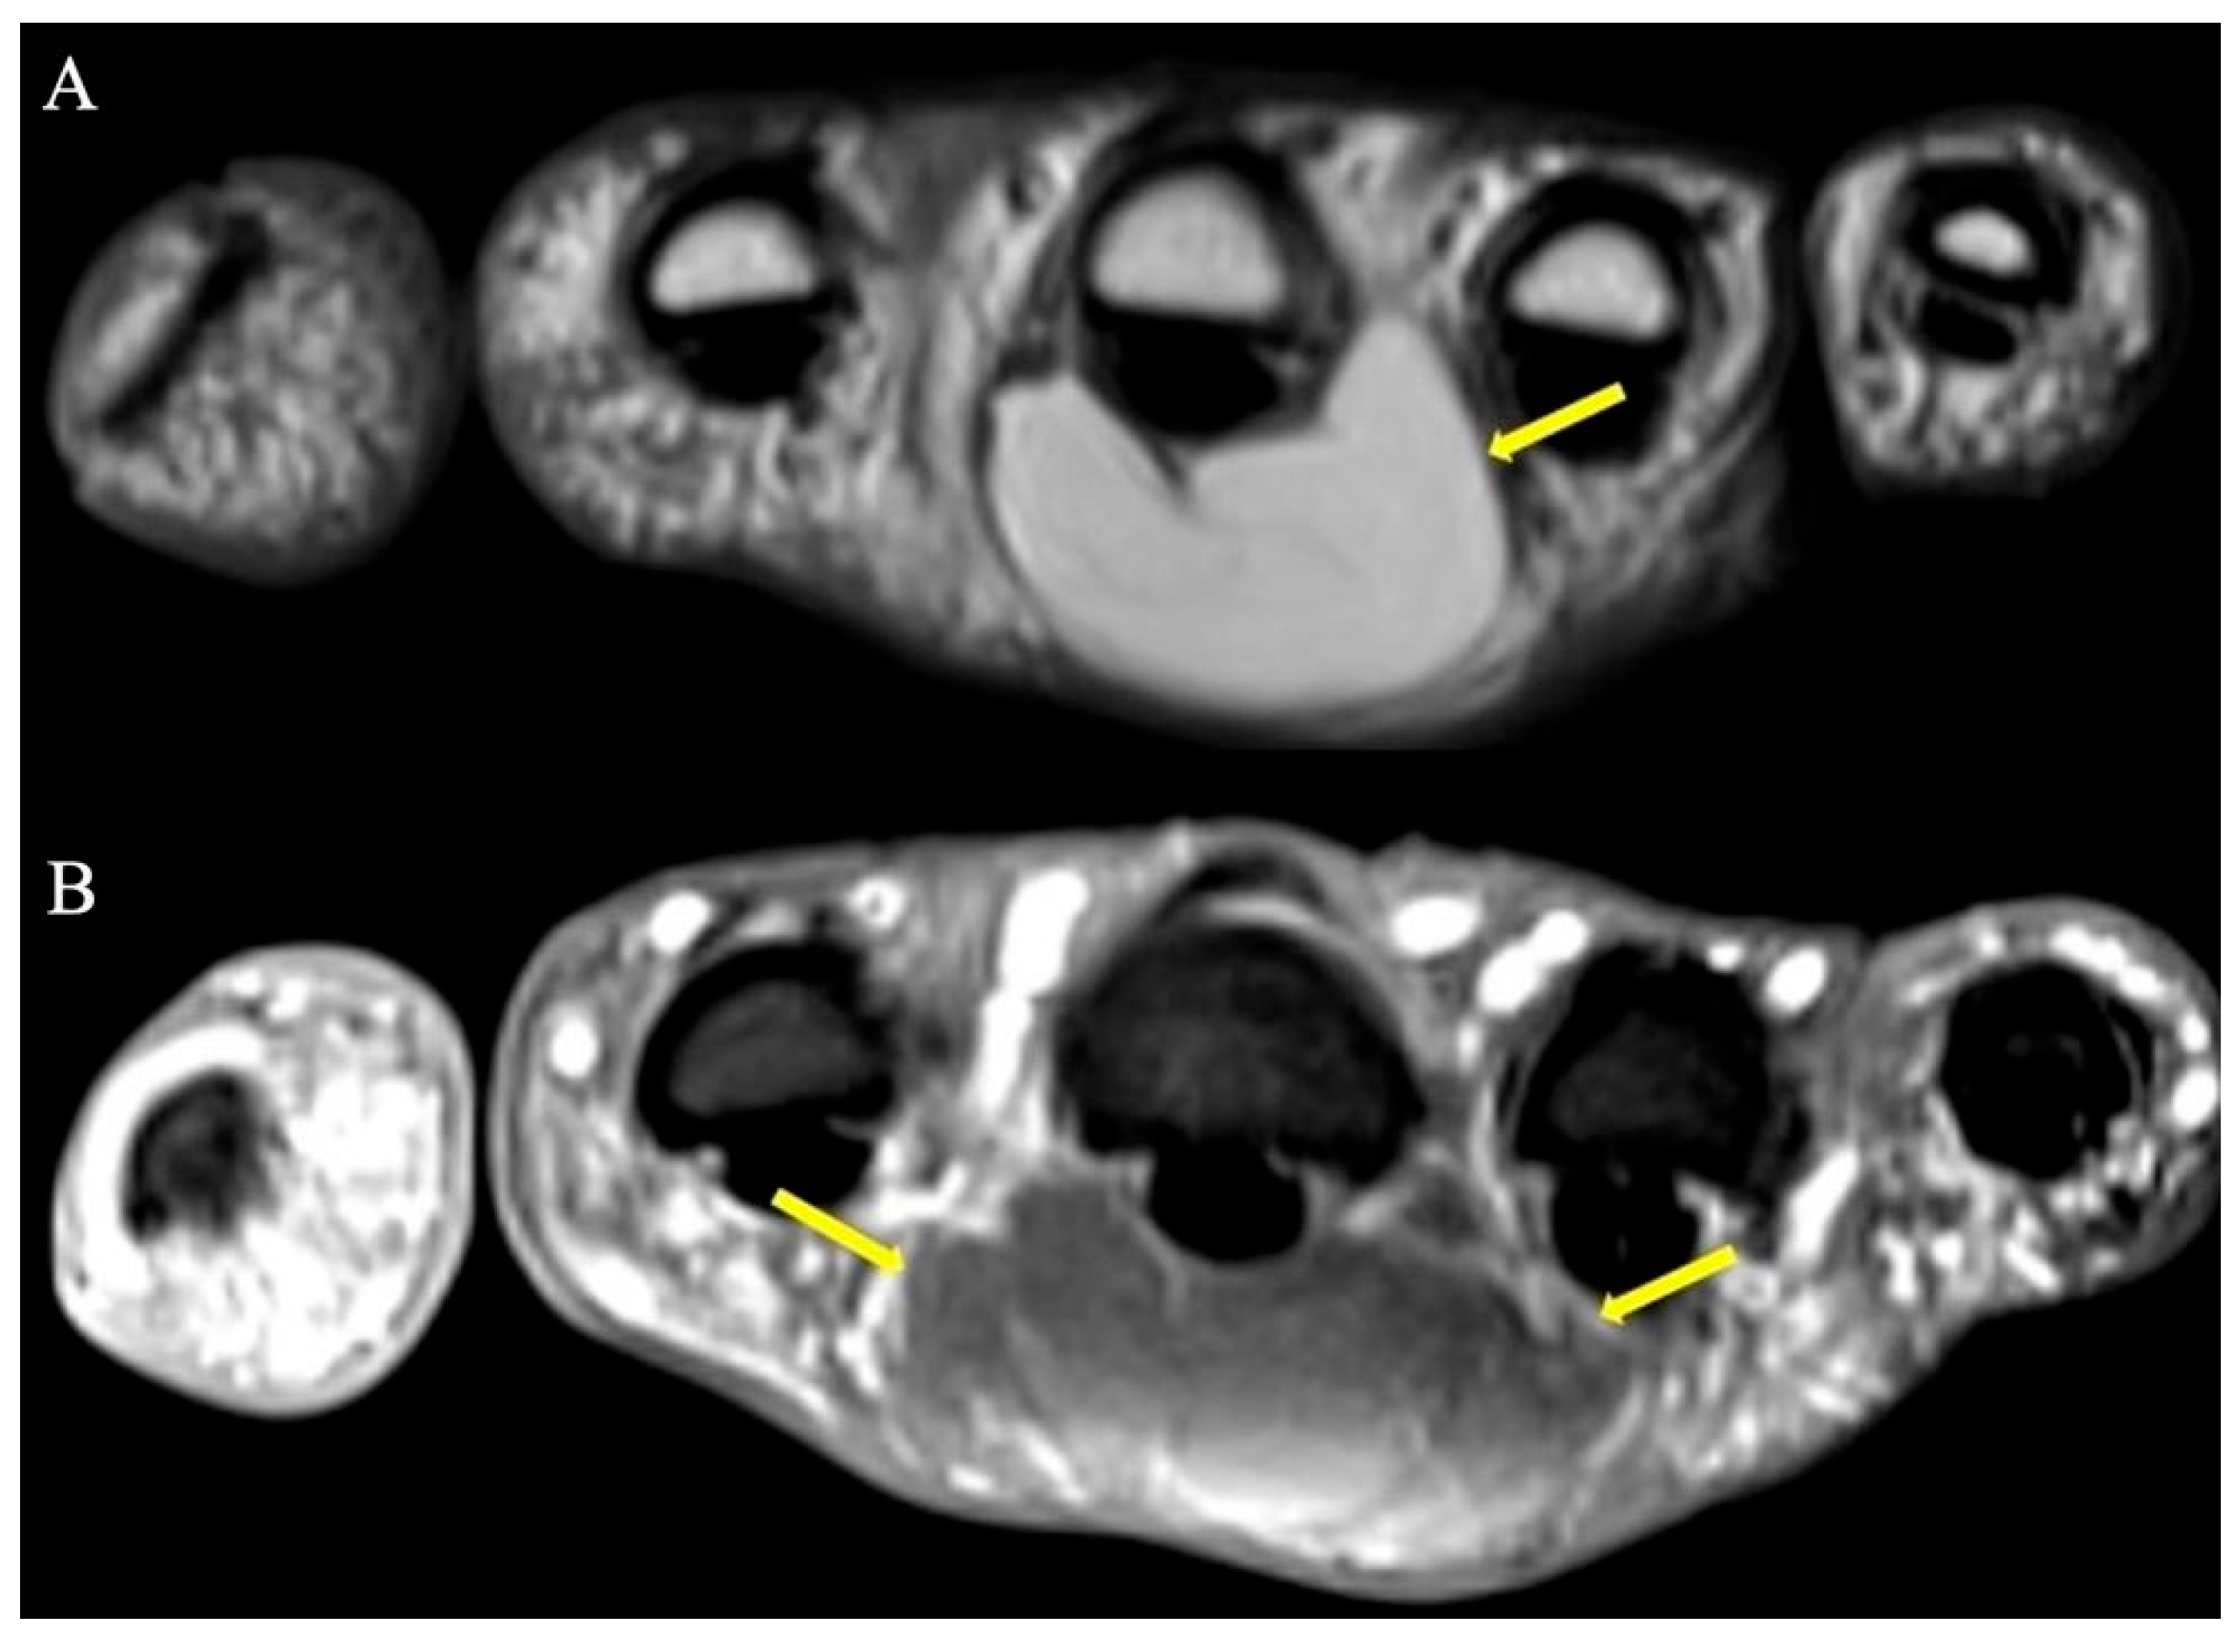

2.8. Synovial Chondromatosis

2.8.1. Clinical Features

2.8.2. Imaging Appearance